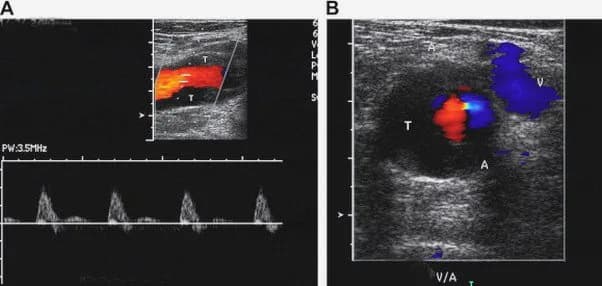

- Siêu âm Doppler: Sử dụng sóng âm để tạo ra hình ảnh về các mạch máu và dòng chảy của máu.